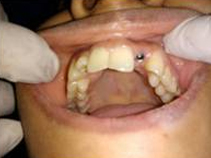

Pre Operation

Single Tooth Implant

Drilled socket for Implant